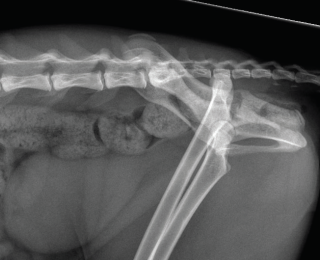

Proximity of the cranial tibial artery to the tibial bone at different angles of stifle extension in the dog: An ex vivo computed tomographic angiographic study

Cranial cruciate ligament disease (CCLD) is the most common cause of pelvic limb lameness in the dog. Tibial plateau levelling osteotomy (TPLO) is one of the most commonly performed procedures to treat CCLD by neutralising cranial tibial thrust and providing dynamic stability to the stifle joint at a standing angle. Excessive haemorrhage during the TPLO procedure has been described as an infrequent but potentially severe intraoperative complication, with a reported incidence of up to 1.6%. Damage to the proximal tibial musculature, cranial tibial artery or its five-way vascular network, or the cranial tibial vein during muscle elevation or performance of the osteotomy has been implicated as the cause of this excessive haemorrhage.1-6 In one study, the authors recommended performing the osteotomy with the stifle in flexion to allow the gastrocnemius muscle to relax and the cranial tibial artery to move caudally, potentially decreasing the risk of injury to the vessel during performance of the osteotomy. However, there have been no studies investigating the proximity of the cranial tibial artery to the tibial bone at different angles of stifle extension in dogs with intact or deficient cranial cruciate ligament. Therefore, the objectives of this study led by Dr Mullins are to: determine the shortest distance between the cranial tibial artery and the tibial bone at different angles of stifle extension in canine cadaveric stifles with an intact CCL and a completely transected CCL; and to investigate whether complete surgical transection of the CCL would result in a significant change in the distance between the cranial tibial artery and the tibial bone at any angle of stifle extension.